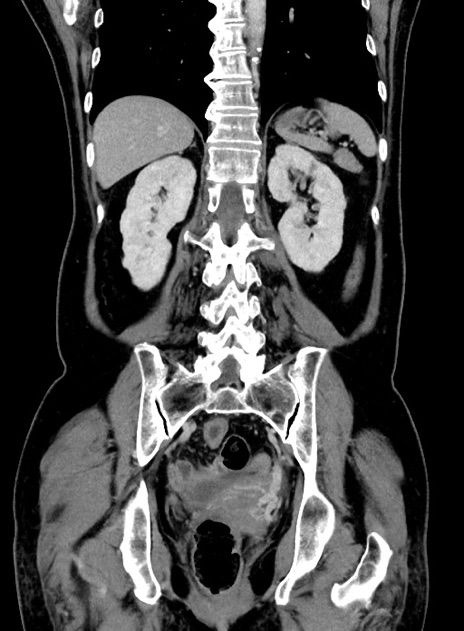

横断像

【症例】 60歳代女性

【主訴】むかつき、みぞおちの痛み

【現病歴】3日前よりむかつきがあり、食事がとれない。

【既往歴】糖尿病

【身体所見】発熱なし、心窩部圧痛軽度あるも、腹膜刺激症状なし。

【データ】WBC 7400、CRP 1.92